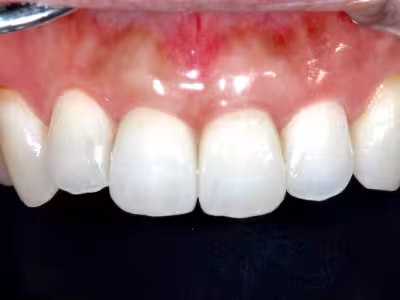

ラミネートべニア

治療前後写真

治療前

治療後

年齢・性別

35歳・女性

来院理由

前歯の審美障害

治療内容

前歯2本の形態を微量形成→精密印象→仮歯で色・形を確認→後日べニアを強固に接着

治療期間

約1ヶ月

費用

310,200円(2本)

リスク・副作用

エナメル質切削に伴う歯髄への影響リスク

接着界面の経年変化

医院コメント

低侵襲で形態・色調を改善。

技工士立会いで色合わせを行い自然感を重視。